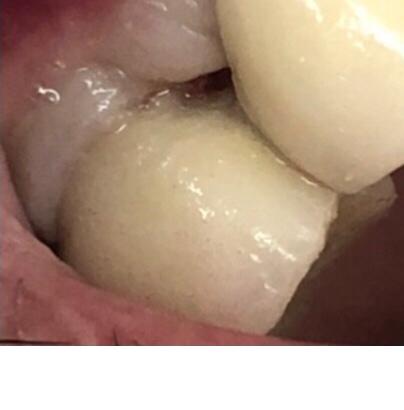

En realidad, lo más notorio de este caso es el uso por primera vez de un tornillo pasante mucho más sofisticado fabricado y distribuido por la empresa Suministros ASATIM. Este tornillo pasante es especial porque está fabricado en cromo-cobalto recubierto de nitruro de titanio. Esto le imprime una gran biocompatibilidad. Y también, al ser aleación de cromo-cobalto presenta mucha más resistencia a la fractura que si estuviera fabricado en aleación de titanio. De hecho el límite de elasticidad de la aleación de cromo-cobalto es el doble al límite de elasticidad de la aleación de titanio.

Con la instalación de este tornillo esperamos una mayor durabilidad de la restauración protésica. Este nuevo tornillo pasante fabricado con unas métricas muy ajustadas al plano mejora la adaptación a las roscas de los implantes. Apostamos por esta nueva tecnología en el tratamiento de nuestros pacientes y con ello esperamos mejorar los resultados de las prótesis sobre implantes.